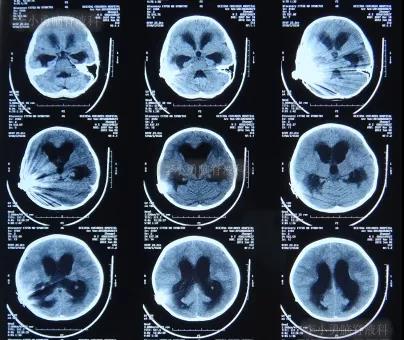

但是在住院第19天即在2012年6月6日时(注:即在人工耳蜗植入术颅内感染并发症21天时),患儿出现了左眼闭合和右侧肢体瘫痪即交叉性偏瘫,以及进食无力和不能交流的病情加重的表现,立即脑CT检查发现了脑积水的表现(图-6)。

图-6:2012年6月6日脑CT脑室扩大显著

2012年6月7日(人工耳蜗植入术后经3家医院治疗近4个月时间内:脑积水颅内感染仍持续加重)住入李小勇脑脊液科,入院时:神志清醒;理解语言能力下降(聋哑);左侧眼睛不能自动睁开与闭合;左侧鼻唇沟消失(即左侧面瘫症状);但是右侧肢体偏瘫无自主活动,疼痛刺激时:右下肢有3级肌力反应;右上肢有1级肌力反应(图-7)。

入院当天脑CT检查发现,脑积水又有加重表现(图-8)。

图-8:2012年6月7日脑CT脑积水加重